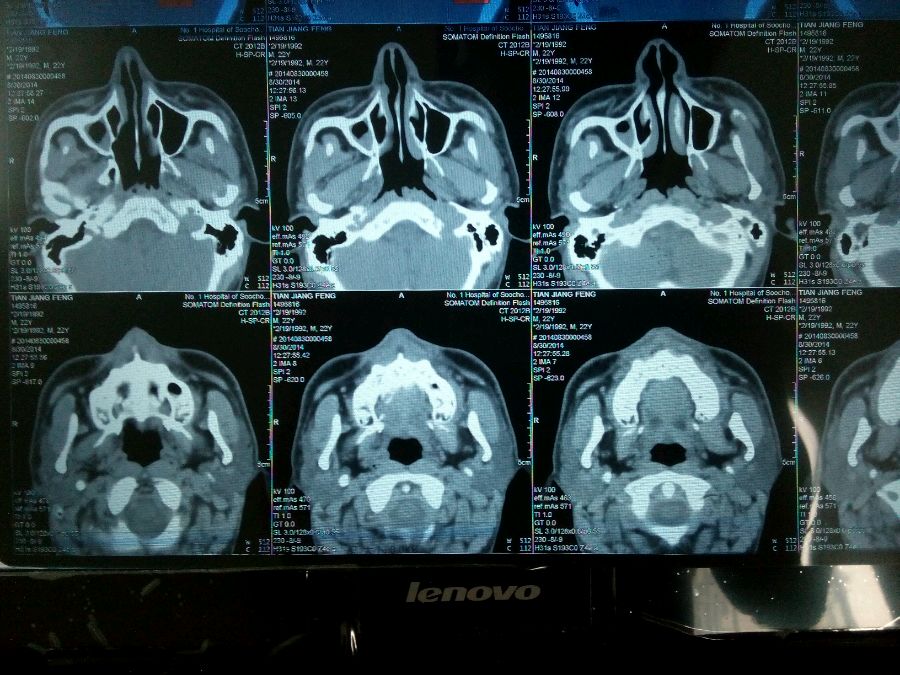

鼻骨骨折?? 鼻炎?鼻窦炎?请高人帮忙看看,谢谢了!

骨折看不清楚,右侧上颌窦积液(血?)

炎